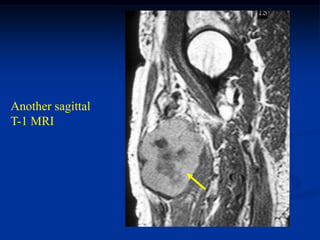

Case #1205

38 year female with

hemangioma forearm

with hypertrophic response

in subadjacent ulna

Bone scan

bone

hypertrophy

Axial PD MRI

Axial gad contrast MRI

Sagittal T-2 MRI

Case #1205 38 yearfemale with hemangioma forearm with hypertrophic response in subadjacent ulna